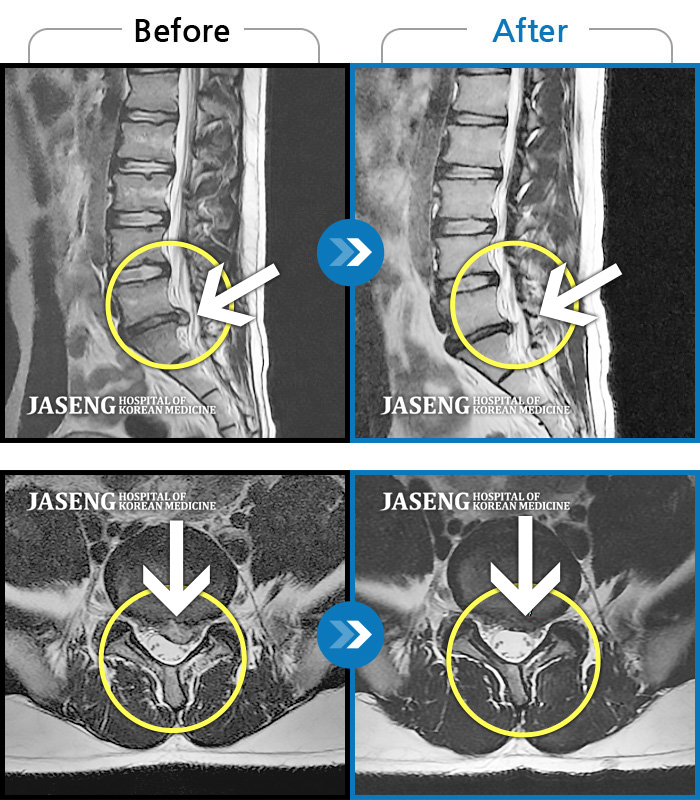

허리디스크

보라매 · 왕오호 원장

좌측 허리 통증과 좌측 다리 저림

촬영시기

2017.08.26 ~ 2018.08.21